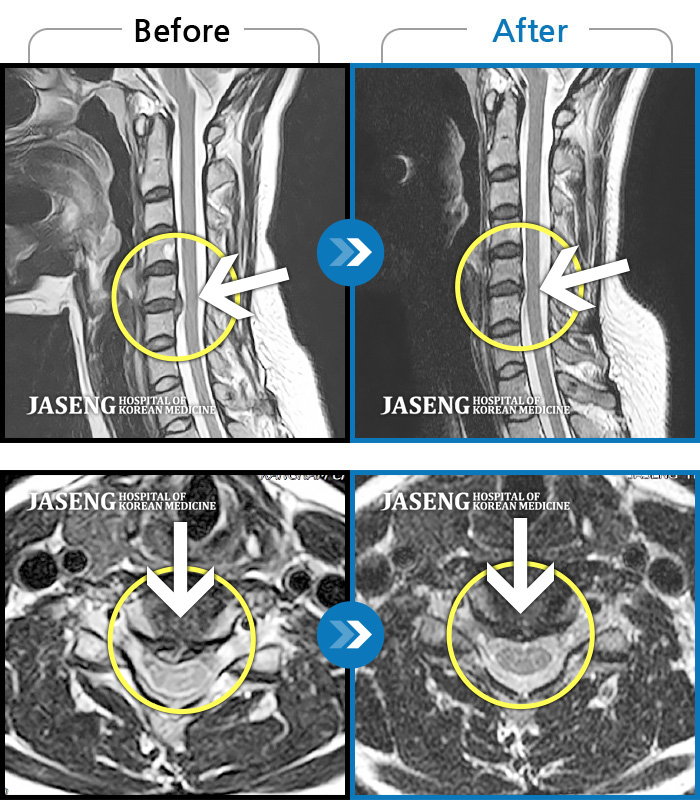

MRI 결과는 추간판협착증 2군데와 추간판탈출되어 터져서 디스크가 좌측으로 흘러내려 좌측 신경을 넓게 누르고 있는 곳이 1군데로 예상보다 심각한 상태였더군요.